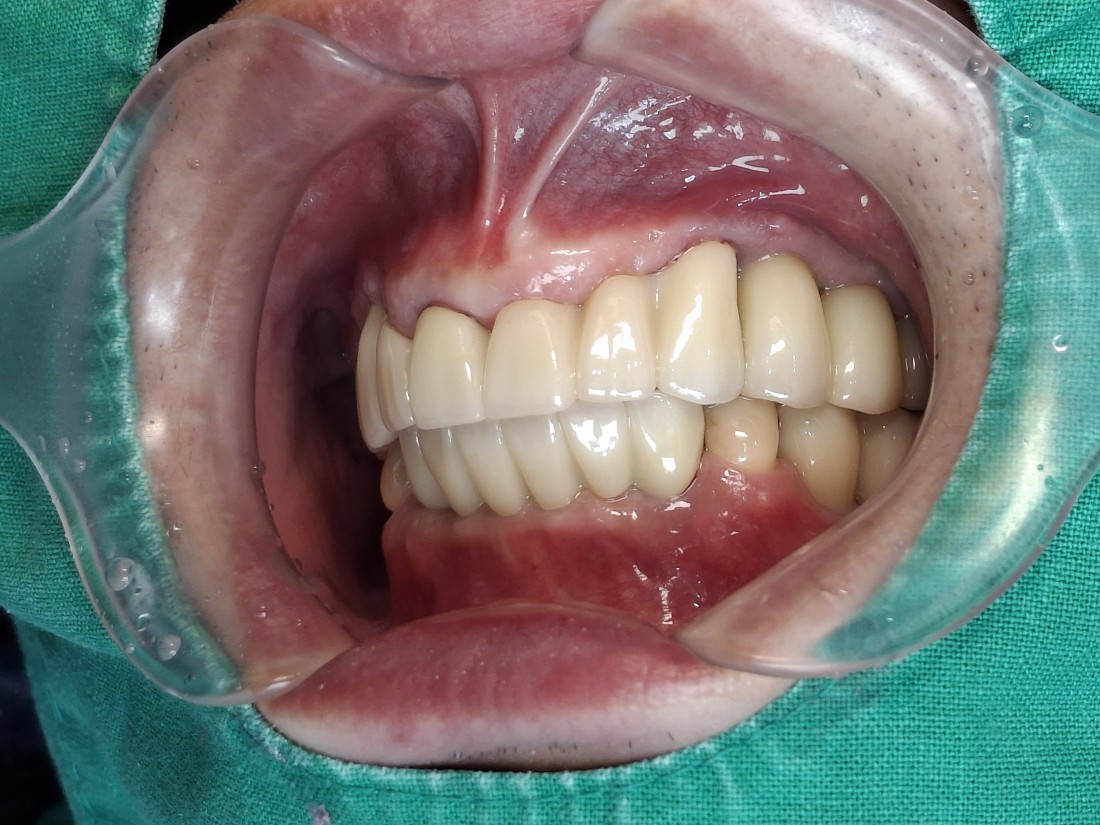

수완동 임플란트 치과는

자체 치아기공소를 운영하고 있습니다.

대표원장인 제가 직접

치아기공소의 보철물 퀄리티를

관리하고 있기 때문에,

무엇보다도

< 예쁘게, 잘 씹어지는 >

수완동 임플란트를 약속드릴 수 있습니다.

잘 관리하면 반영구적으로 사용할 수 있는

임플란트이기 때문에

특히 자연치아보다 더 자연스러운

아름다운 임플란트를 완성하는

수완동 임플란트 치과입니다.